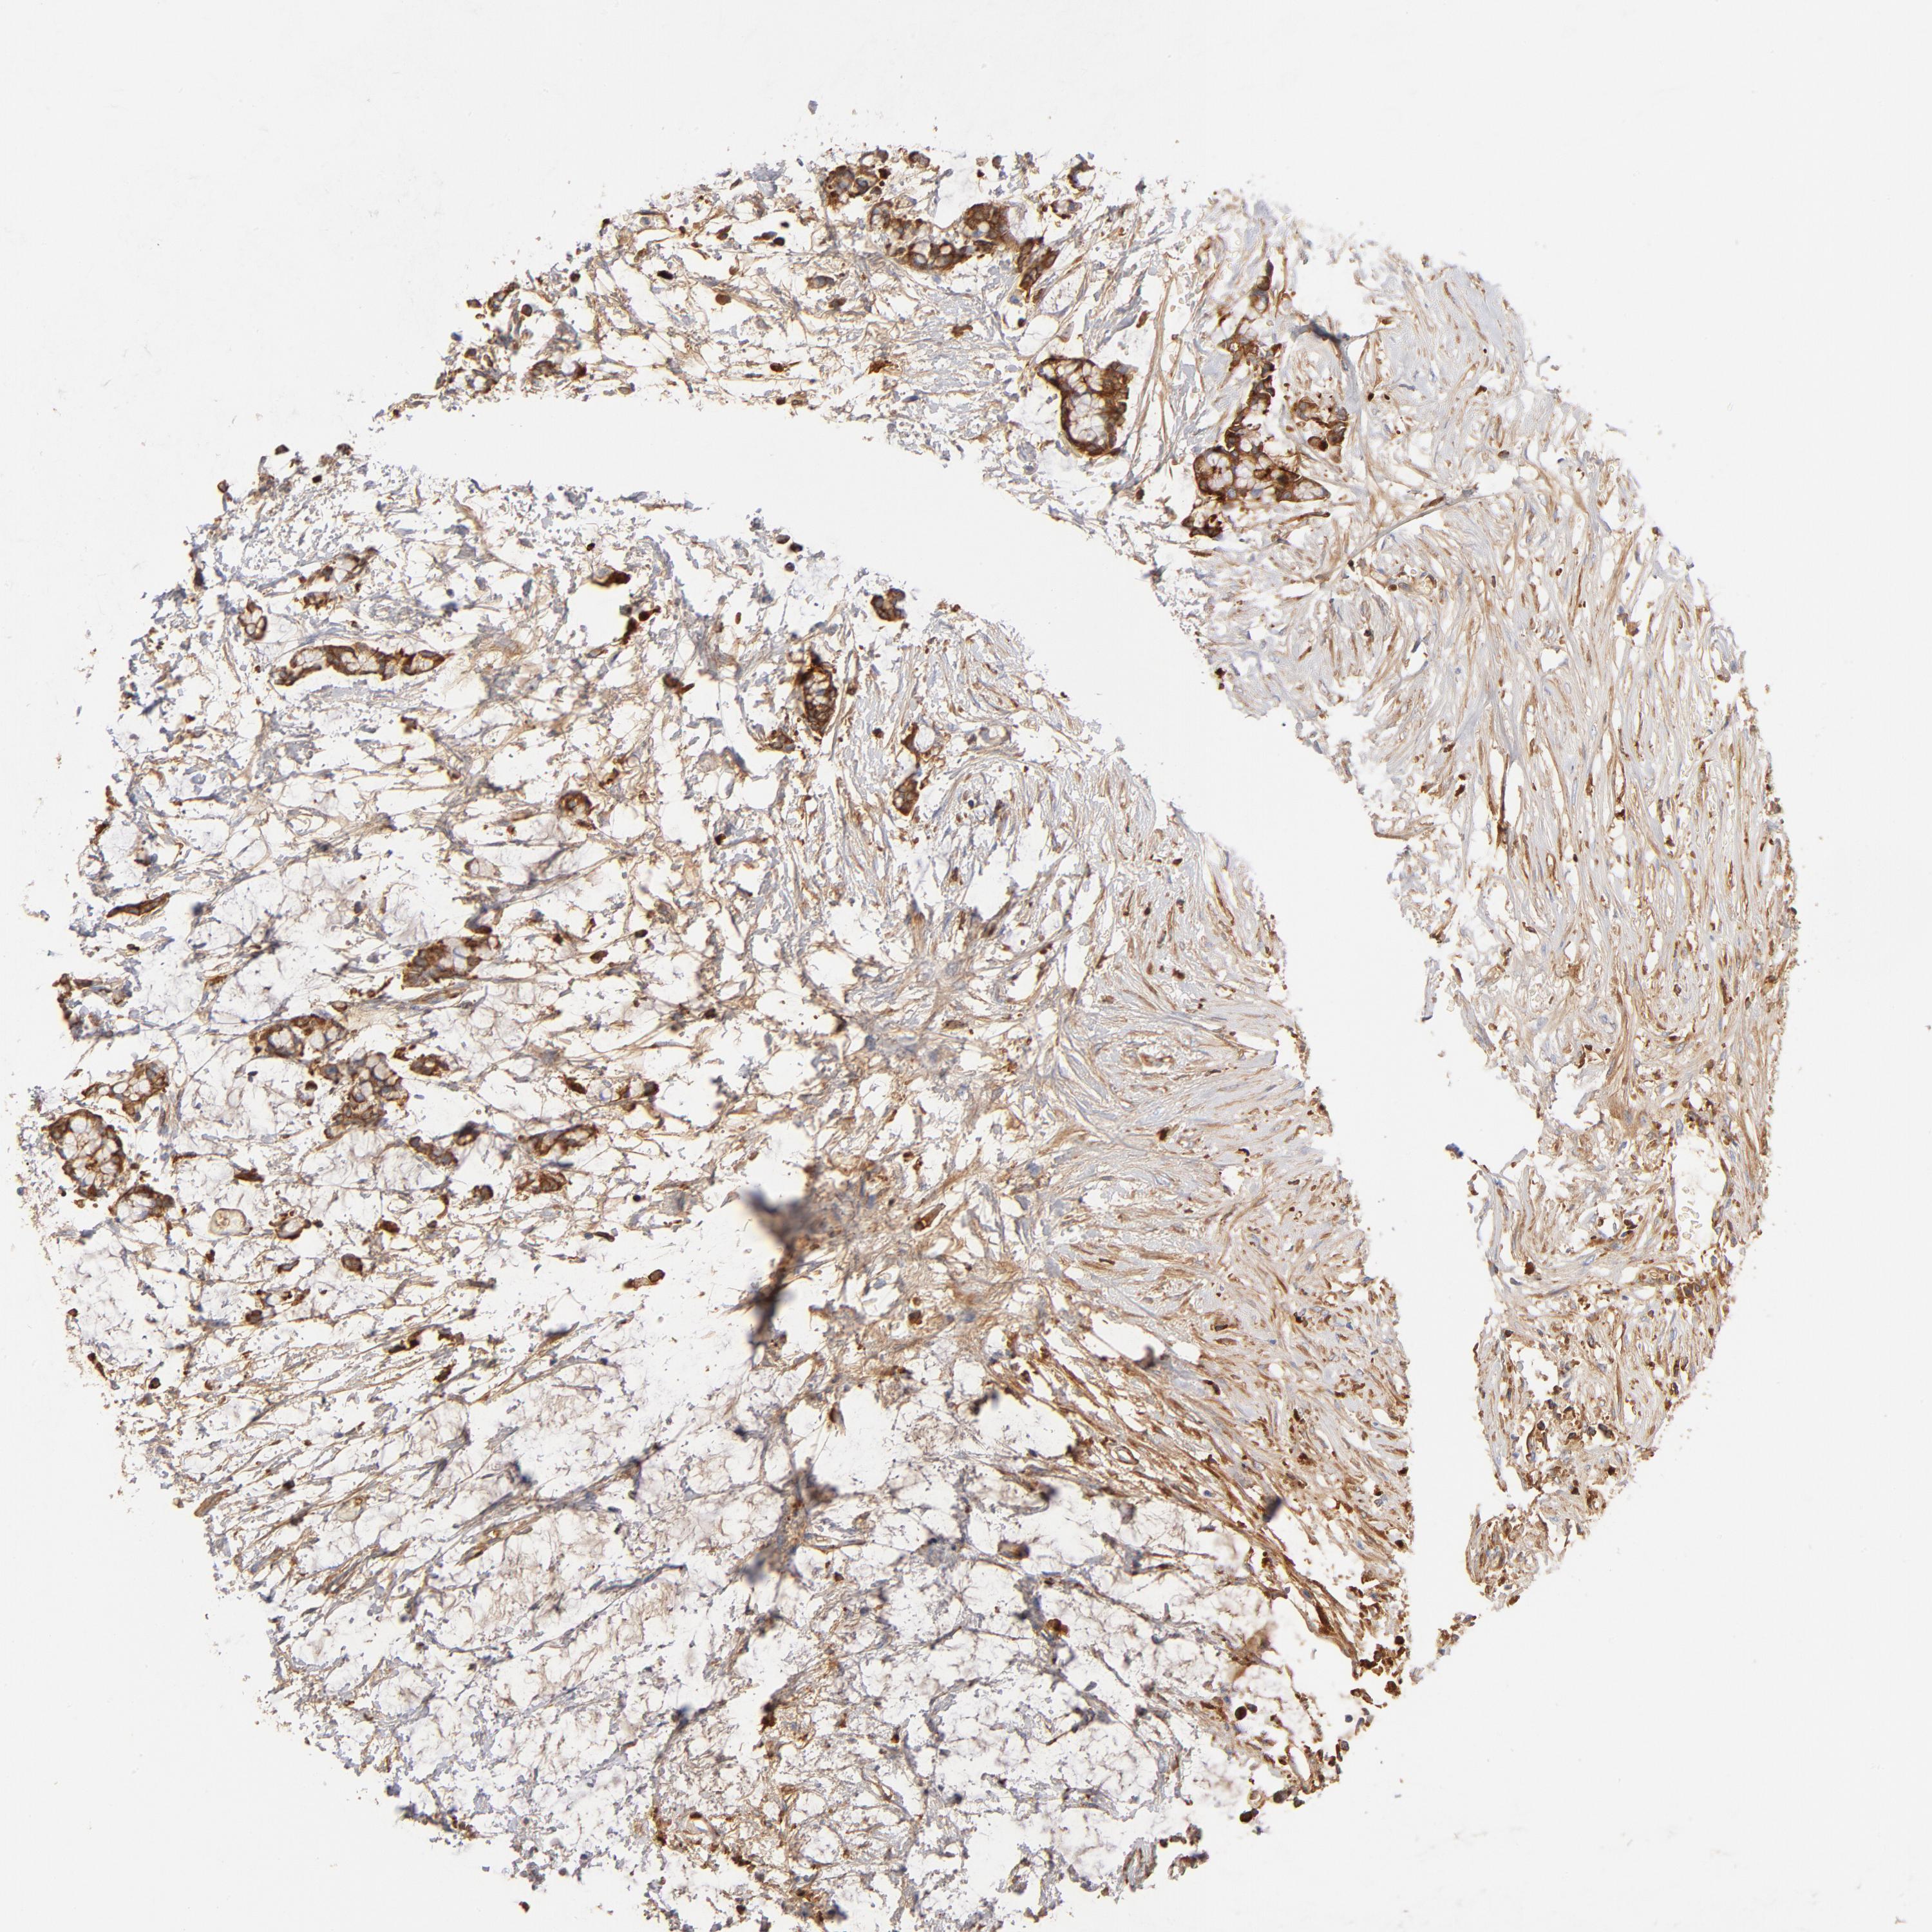

CANCER COLORECTAL CANCER Show tissue menu

Colorectal cancer

Human cancer

Colon adenocarcinoma